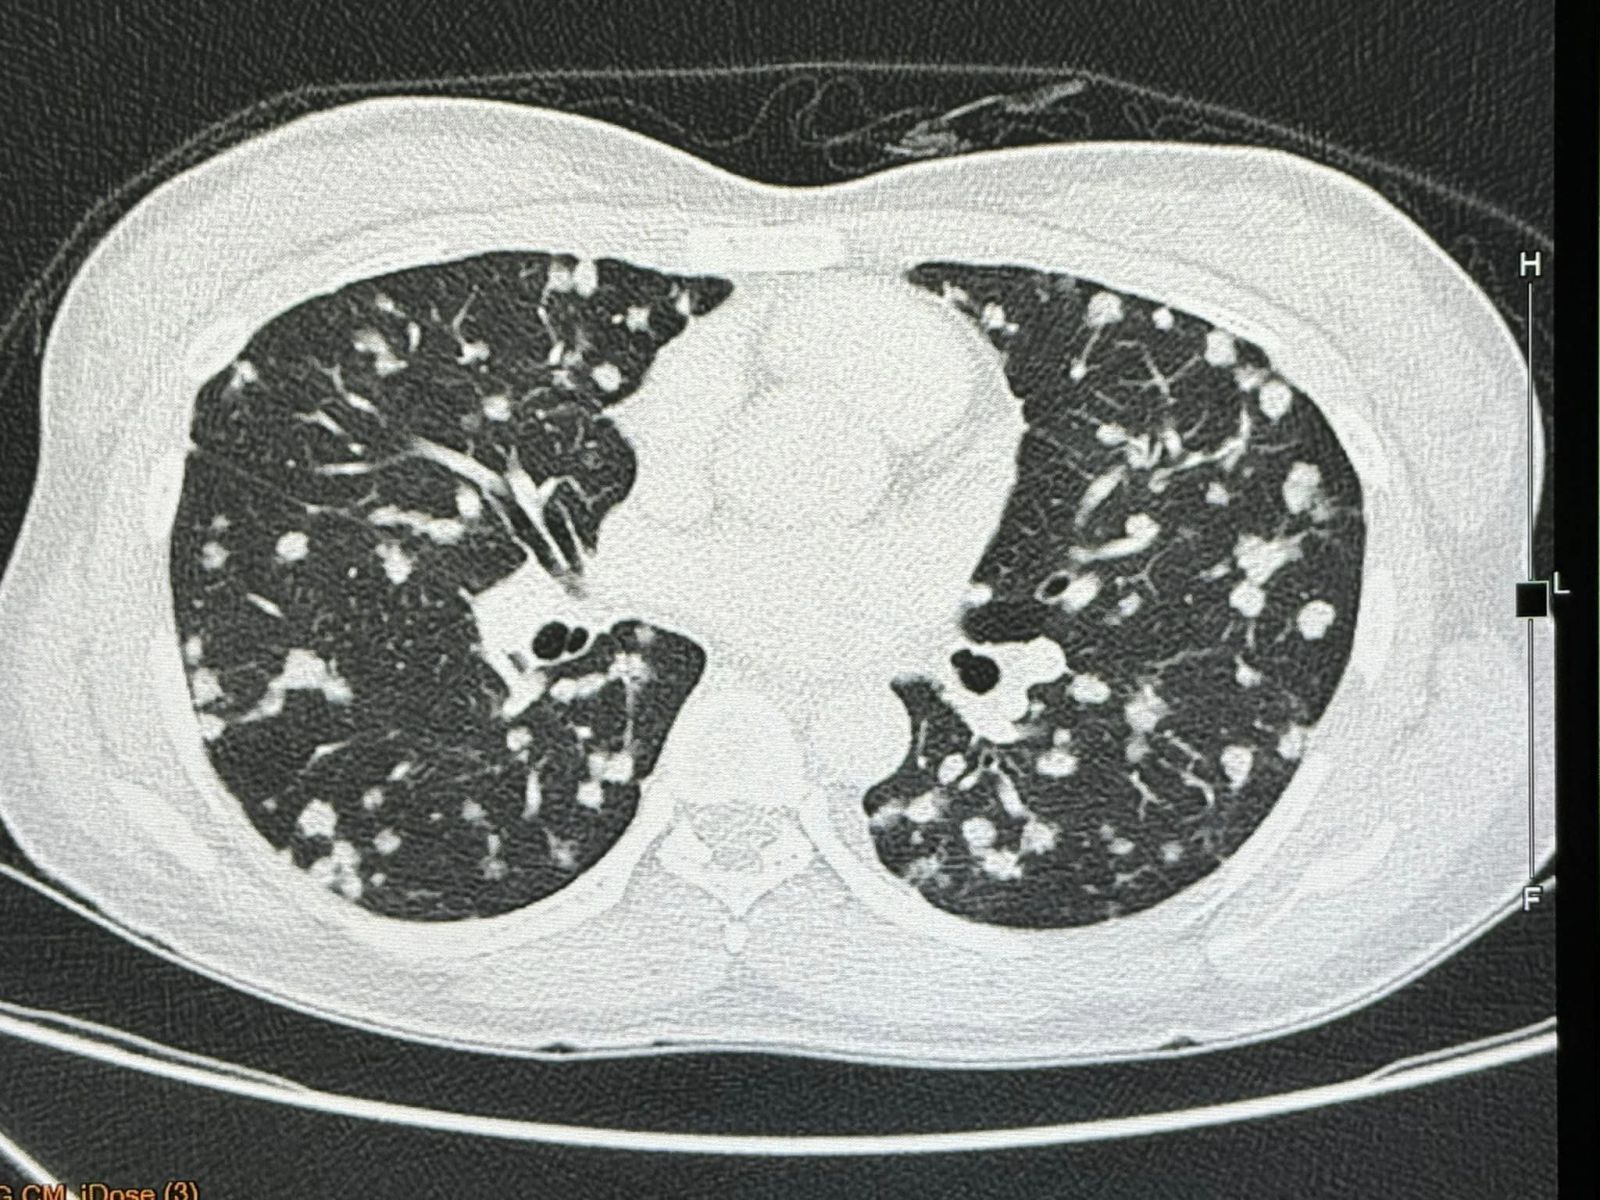

15 กุมภาพันธ์ 2567 นพ.มนูญ ลีเชวงวงศ์ แพทย์เฉพาะทางด้านโรคระบบการหายใจ โรงพยาบาลวิชัยยุทธ โพสต์เฟซบุ๊กรูปภาพฟิล์มเอกซเรย์ พร้อมระบุข้อความว่า ผู้ป่วยหญิงอายุ 38 ปี เป็นโรคเลือดจางและเกล็ดเลือดต่ำ 6 ปี ไม่มียาประจำ ไม่กินเหล้าไม่สูบบุหรี่ ไม่มีอาการ ไม่มีไข้ ไม่ไอ ไม่เหนื่อย น้ำหนักไม่ลด ไปตรวจร่างกายประจำปี เอกซเรย์ปอดพบมีจุดเล็กๆ จำนวนมากกระจายในปอดทั้ง 2 ข้าง

ตรวจร่างกายปกติ ฟังปอดปกติ ระดับออกซิเจนในเลือดปกติ เจาะเลือดเม็ดเลือดแดงและเกล็ดเลือดต่ำเล็กน้อย ค่าตับไต ปกติ ค่ามะเร็งทุกตัวปกติ ทำคอมพิวเตอร์ปอดและช่องท้อง พบจุดเล็กๆ ในปอดขนาด 0.8 เซนติเมตรกระจายทั่วปอด และมีก้อนในตับขนาด 3.4 เซนติเมตร ได้ทำการเจาะเนื้อในตับ ย้อมและเพาะเชื้อ ไม่พบเชื้อราและเชื้อวัณโรค ส่งชิ้นเนื้อตรวจพยาธิวิทยา พบ Epithelioid hemangioendothelioma ติดตามผู้ป่วยนับจากวันที่มีเอกซเรย์ปอดผิดปกติ ถึงปัจจุบัน 6 เดือนแล้ว ผู้ป่วยยังไม่มีอาการ